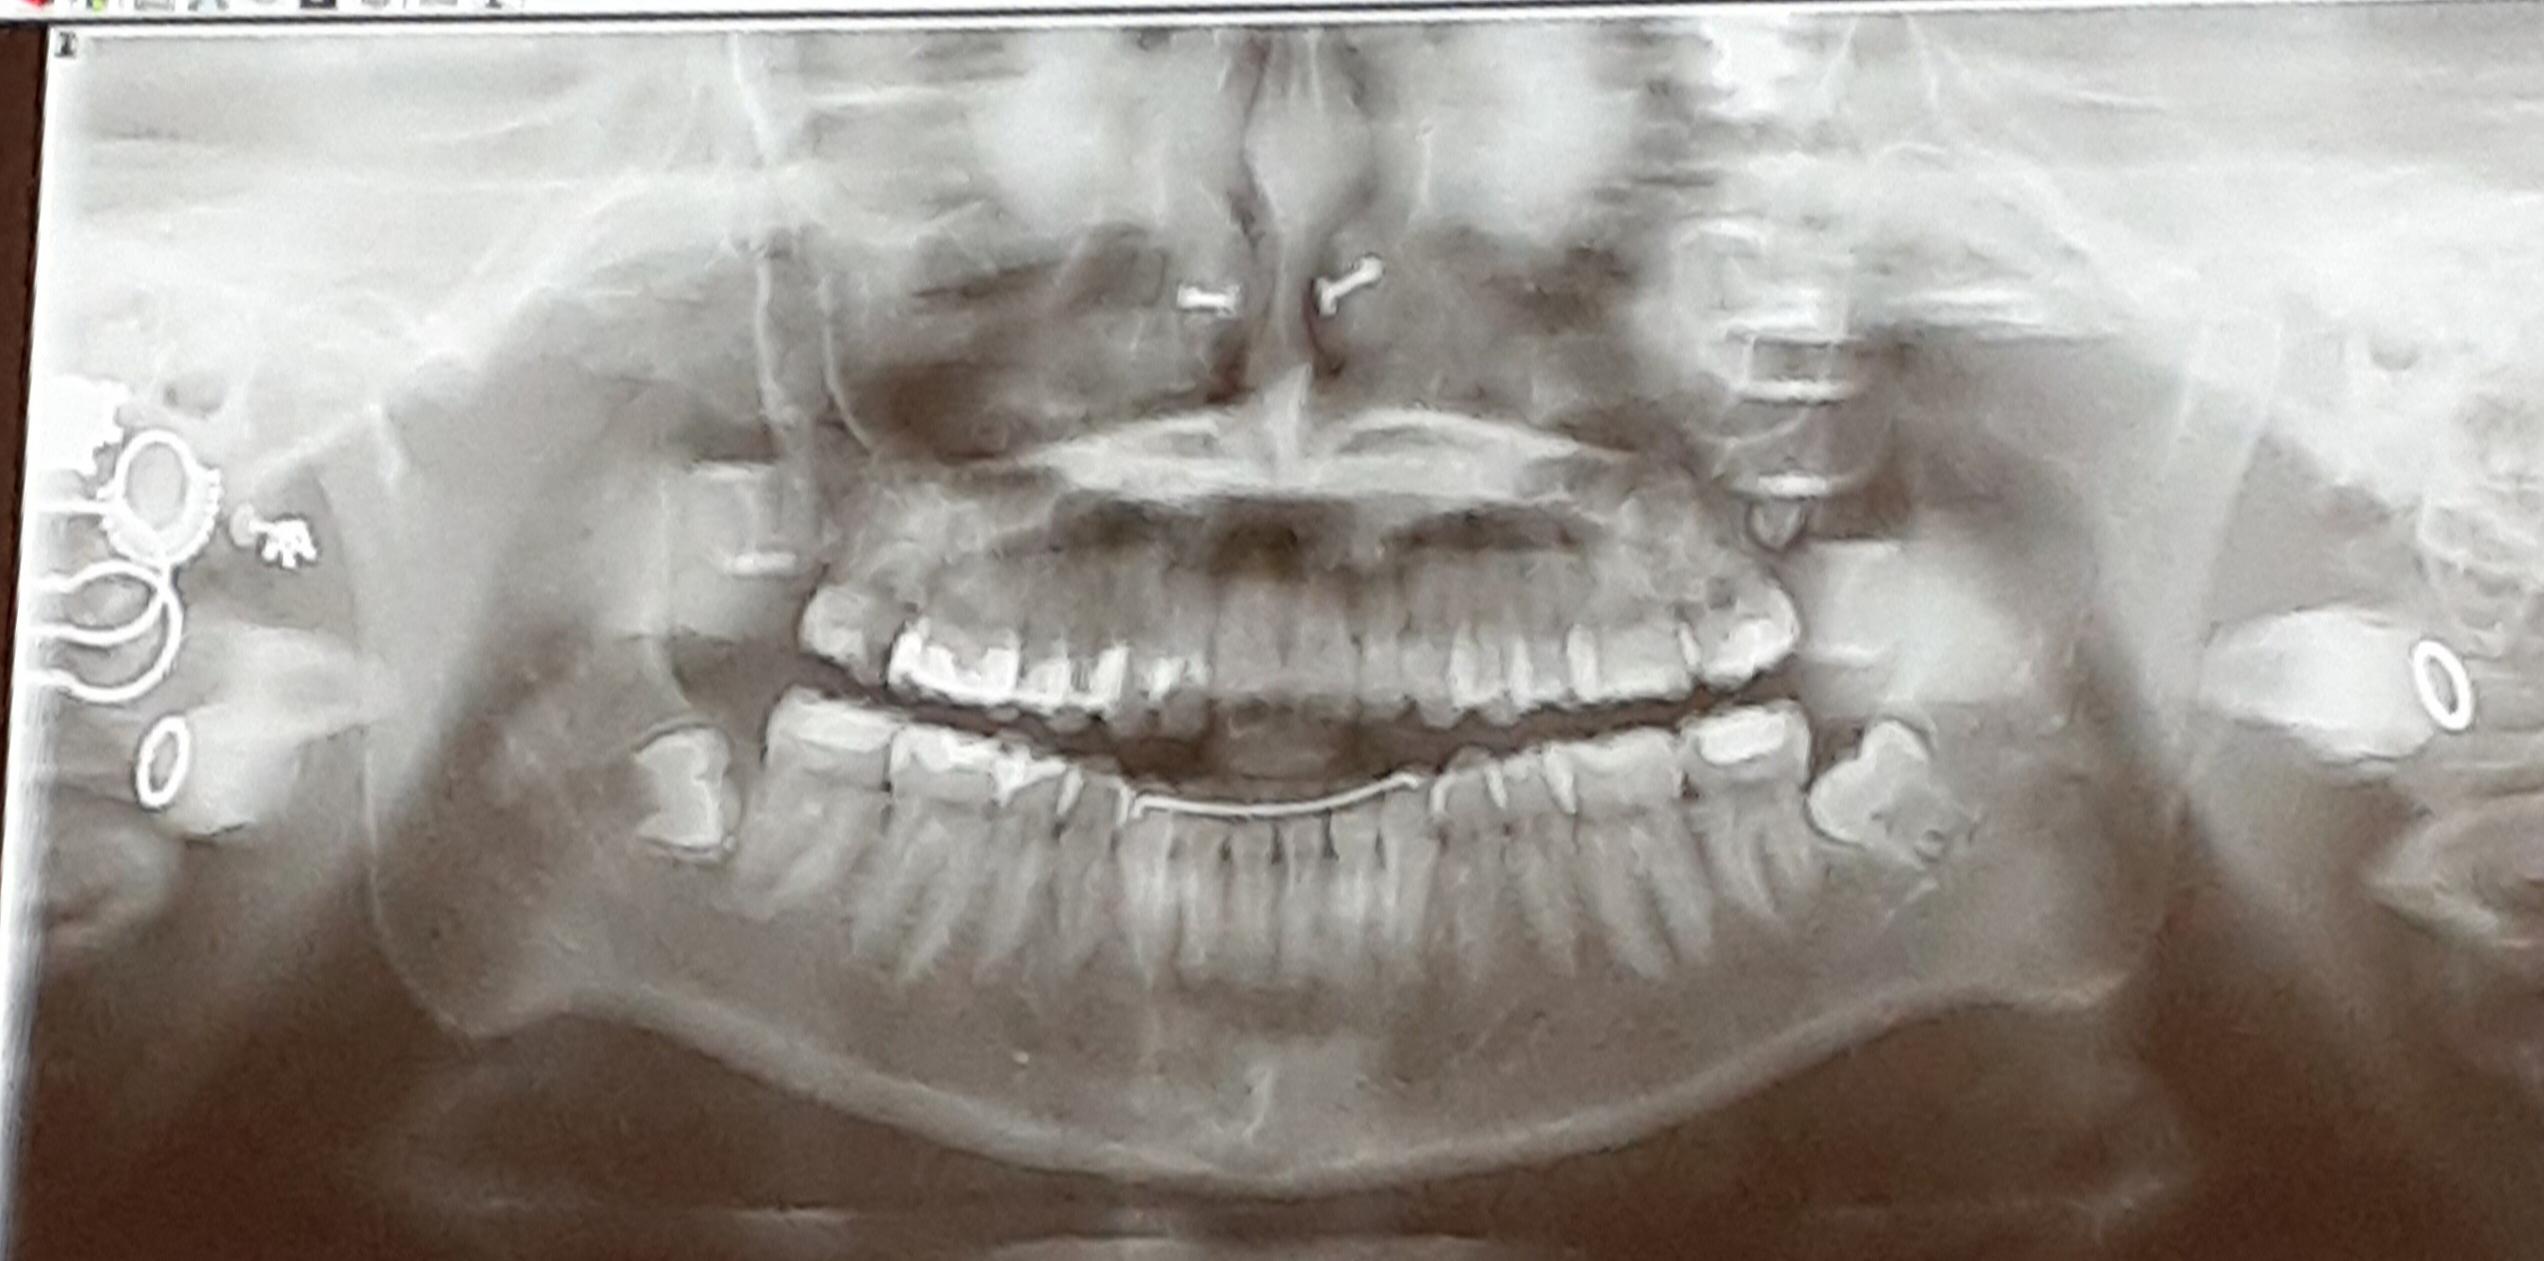

Septum ring shows up in dental xray r/piercing Dental X Rays And Piercings This image depicts the entire upper. Tongue piercing results in dental and. By avoiding production of these artefacts when possible, we can reduce radiation exposure to patients while obtaining the most diagnostically. Before deciding on an oral piercing, consider discussing it with your dentist beforehand. Panoramic radiography is a commonly used imaging technique in radiology and may be a component. Dental X Rays And Piercings.

Septum piercing in Xrays at the dentist r/mildlyinteresting Dental X Rays And Piercings Tongue piercing results in dental and. Before deciding on an oral piercing, consider discussing it with your dentist beforehand. By avoiding production of these artefacts when possible, we can reduce radiation exposure to patients while obtaining the most diagnostically. But what is a dental piercing? What are its effects on oral health, and are there any risks? Panoramic radiography is. Dental X Rays And Piercings.